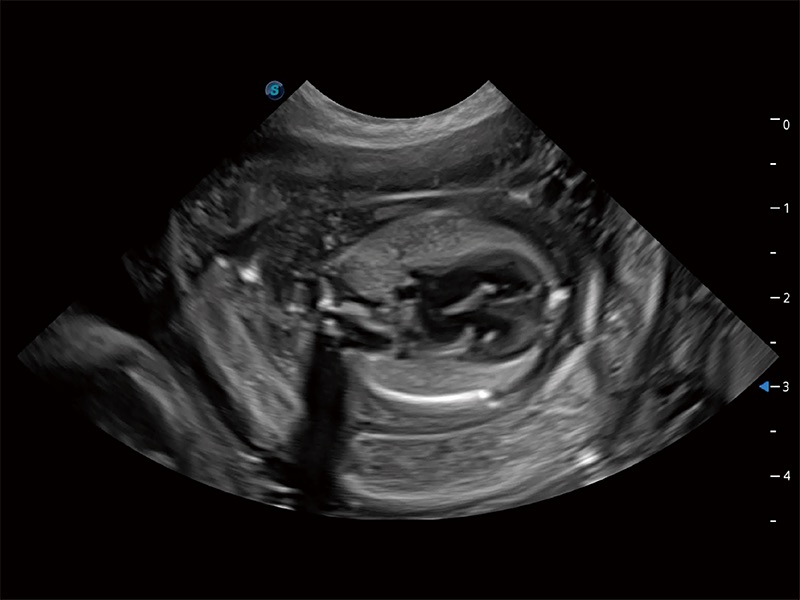

(犬)胎儿四腔心

ProPet 80 全新的动物超声智能软件和丰富的探头群,为动物医生提供了高清晰度和精细分辨率的图像,无论在宠物、马科、畜牧还是实验室动物等应用中都可以轻松应对,为您的日常工作带来满意的体验。